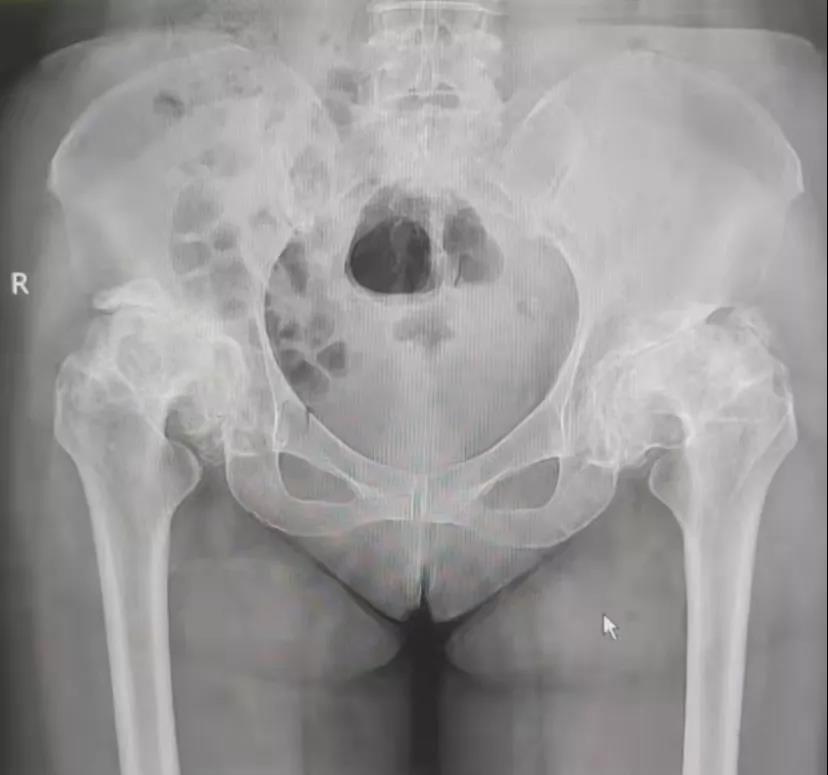

封女士今年也是61岁,病程更久,10余年前就出现了双髋部疼痛、行动不便。近两年来疼痛明显加重,不能下蹲,上、下楼梯困难,日常活动影响较大。封女士也曾到多家医院和私人诊所诊治,病情没有得到改善。受病痛折磨10余年之久,前几天已到南宁某三甲医院住院,准备择期手术治疗。 ※封女士术前骨盆平片

廖女士经多方打听,知悉玉林市中西医结合骨科医院对此类疾病治疗效果很好,约封女士回来,找到髋关节一科黎观保主任一同进行诊治。经过黎观保主任仔细体格检查,结合影像学等相关资料,对廖女士和封女士的病情进行综合分析,廖女士双侧股骨头缺血性坏死,负重区塌陷,FicatⅣ期。封女士双侧髋关节发育不良并骨性关节病,关节间隙明显变窄,骨赘增生明显,关节屈伸旋转活动严重受限。两位病友双髋部疼痛,功能受限严重影响了她们的生活质量。根据她们的病情,黎观保主任与她们进行了详细的病情沟通,她们也选择了先行一侧髋关节置换手术的方案。于2021年11月22日,在麻醉科的积极配合下,黎观保主任为廖女士行“左侧人工全髋关节术”,为封女士行“右侧的人工全髋关节置换手术”,术中均采取DAA入路,应用Anterior Path微创关节置换技术。此技术创伤轻、出血少,人工关节安装精确,术后疼痛轻。黎观保主任鼓励她们术后从手术室走出来,“这可能吗?”廖女士、封女士满脸充满了疑虑,听说以前做手术还要在床上躺半个多月呢。经过黎主任的鼓励,加上术后自身的良好状态,从小心翼翼的试探到慢慢的从容下地,患者从手术室走出来了。